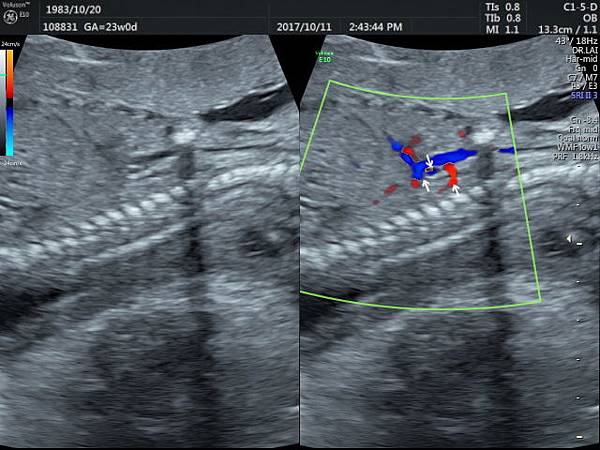

孕兒診所備忘錄 293 right side eparterial bronchus

711-293

right side eparterial bronchus